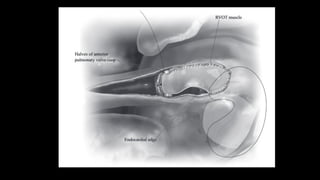

• Figure 4 Attention is now directed toward the RVOT and pulmonary valve. The pulmonary

valve is inspected and the number of cusps, their

consistency, the level of fusion, thickness, and the depth of the sinuses of Valsalva are

noted. A Hegar dilator is passed to measure the effective

orifice, NOT to dilate the valve. The cusps are thinned out gently, and each commissure is

incised with a no. 15 scalpel blade down to the

medial layers. Measure of the new effective orifice is now done again with Hegar dilators.

These maneuvers usually gain an additional 1-2 mm

in effective orifice diameter. Depending on the theoretical pulmonary annular size in

relation to the body surface area, a decision is made

about whether to stop or proceed with balloon dilation or pulmonary valve patch

augmentation. A rough estimate is that if the effective orifice

is within 1 mm of expected effective orifice for body surface area, nothing else is done. If

the effective orifice is o2 mm from expected, slow

and deliberate hand-controlled balloon dilation (Fig. 5) using as a first balloon diameter the

size of the orifice measured after sharp

commissurotomy. If the orifice is considered too small and an incision across the

pulmonary annulus is deemed necessary, then patch

augmentation of the pulmonary valve by division of the pulmonary annulus and anterior

cusp in the midline, using the 2 divided halves of the

anterior cusp to anchor the patch, is done (Fig. 6). PA = pulmonary artery.

• Figure 6 Once a decision has been made to divide

the annulus, both RVOT and PA incisions are

joined. Most TOF pulmonary valves have a

well-developed anterior cusp that is in the sagittal

plane. That cusp is divided in the midline (Fig. 7).

The tethering of the anterior cusp to the

MPA is left untouched to preserve hinge function

of the newly created large anterior cusp. If the

patient has a commissure in the anterior

midline, then the incision is made through that

commissure. MPA = main pulmonary artery